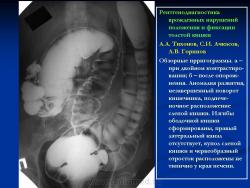

Варианты и аномалии развития толстой кишки.